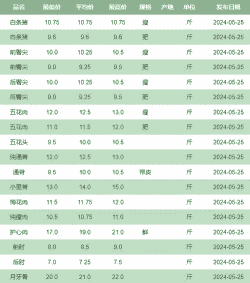

治疗肉鸡腹水症的方法有以下几种:

饲料调整早期限饲:从13日龄起对肉仔鸡每天减少饲料量10%,维持2周,然后恢复正常饲养。限饲对降低腹水症的发生率有显著效果。

营养水平调整:在3周龄前饲喂低能日粮,之后转为高能日粮。具体实施方案为:1-3周龄,粗蛋白20.5%-21.5%,代谢能量11.91-12.33 MJ/kg;4-6周龄,粗蛋白18.5%-19.5%,代谢能量12.54-12.75 MJ/kg;7周龄至出栏,粗蛋白13%,代谢能量12.75-12.96 MJ/kg。

双氢克尿噻:每只鸡每天口服6毫克,每日2次。

维生素C:在新鸡的饲料中按每公斤饲料100毫克的量加入,连用3日。

抗生素:无菌操作用针管抽取腹腔积液,然后注入0.05%的青霉素普鲁卡因0.2-0.3 mL,1%速尿注射液0.3 mL,严重病例同时肌注10%安钠加0.1 mL。全群饮水中加入0.05%维生素C,或在饲料中添加氯化钙、利尿剂、健脾利水的中草药等。

光照管理间歇光照法:2周龄开始晚间采用间歇光照法,即2-3周龄光照1小时,黑暗3小时;4-5周龄光照1小时,黑暗2小时;6周龄至出栏光照2小时,黑暗1小时。

饲料搭配:严格按照肉鸡的生长需求提供优质的饲料,禁止投喂变质、劣质和高油脂的饲料。保证饲料中各营养素的充足和均衡,尤其是钙和磷。

综合以上方法,建议采取综合防治措施,包括中药治疗、饲料调整、药物防治、光照管理和环境管理,以有效降低肉鸡腹水症的发生率和死亡率。一旦发病,应及时隔离病鸡并进行对症治疗,同时注意防止继发感染。